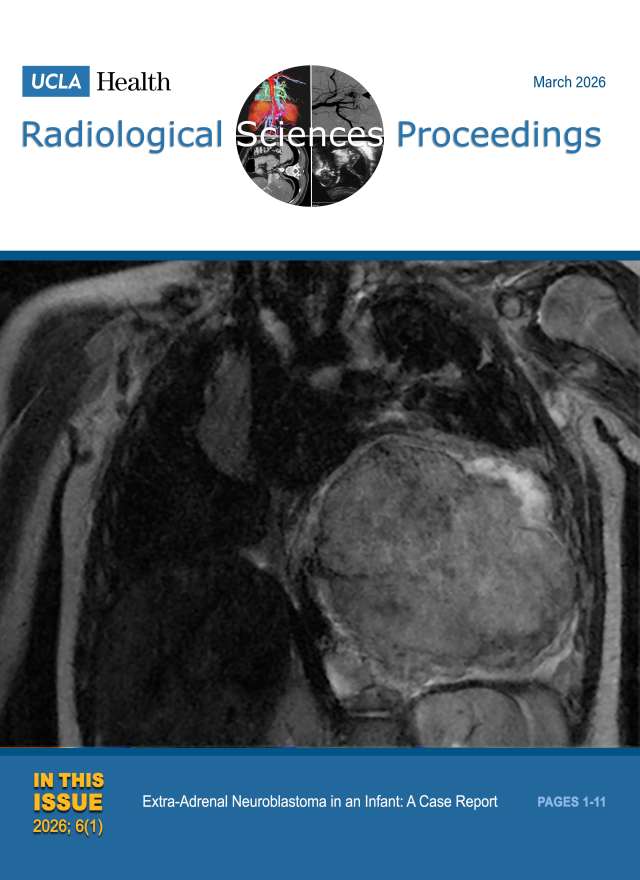

December 2024

Volume 4, Issue 4

- Smoking-Related Interstitial Lung Disease: CT Image-Based Review and Update

- Postcholecystectomy Syndrome due to Prominent Remnant of the Cystic Duct and Choledocholithiasis: A Case Report

- Kommerell Diverticulum and Agenesis of the Left Common Carotid Artery in a Patient with Dysphagia: A Case Report

- Extensive Subcutaneous Calcinosis and Hypercalcemia in the Setting of Mineral Oil-Injection-Related Foreign Body Reaction: A Case Report